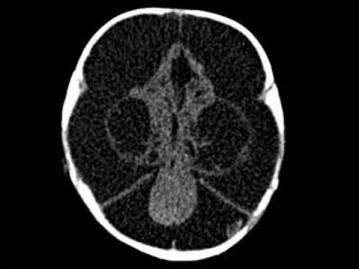

问题 3个月男婴,头颅迅速增大,发育停滞,CT表现如图,可能的诊断为 ( )

选项 A、先天性脑积水 B、重度脑积水 C、慢性双侧性巨大硬膜下血肿 D、水瘤 E、脑严重缺血

答案 A